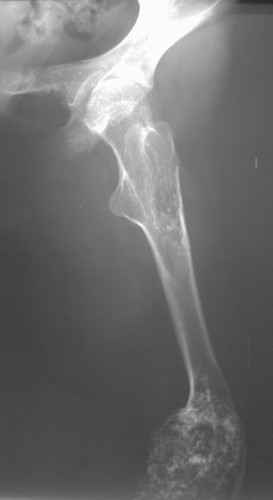

Деформация правой нижней конечности с 6 месяцев (стала прогрессировать после года, с момента начала ходьбы). Поставлен диагноз болезнь Олье, варусная деформация, укорочение правой нижней конечности на 4,5 см. 1993 г. - операция остеоклазия на уровне очагов поражения в н/3 правой бедренной кости и в/3 правой большеберцовой кости с одномоментной коррекцией деформации и фиксацией костных фрагментов спицами Киршнера.После начала статической нагрузки (1994 г.) появился рецидив деформации и укорочения. Вторая операция - ЧКО АВФ, аппарат демонтирован через 2недели в связи с развившимся на уровне стержня переломом, после чего находилась в гипсовой повязке до консолидации костных фрагментов. Далеелечилась консервативно в гипсовой повязке. Выраженная деформация и укорочение правой нижней конечности. Относительная длина бедер: справа -34 см, слева - 51 см; анатомическая длина голеней: справа - 29 см, слева - 39 см. Величина варусной деформации на уровне дистального отдела правого бедра составляет - 80 град. Амплитуда движений в коленных суставах (разгибание/сгибание ): справа - 0/0/100 град.; слева - 0/0/30 град. Отмечается боковая и ротационная нестабильность на уровне правого коленного сустава. Амплитуда движений в голеностопных суставах - в норме. Тактика лечения? Заранее благодарю! С уважением,А.В.Владзимирский

Высылаю вам фото подобной больной, у нее тоже первая попытка до меня была безуспешной.